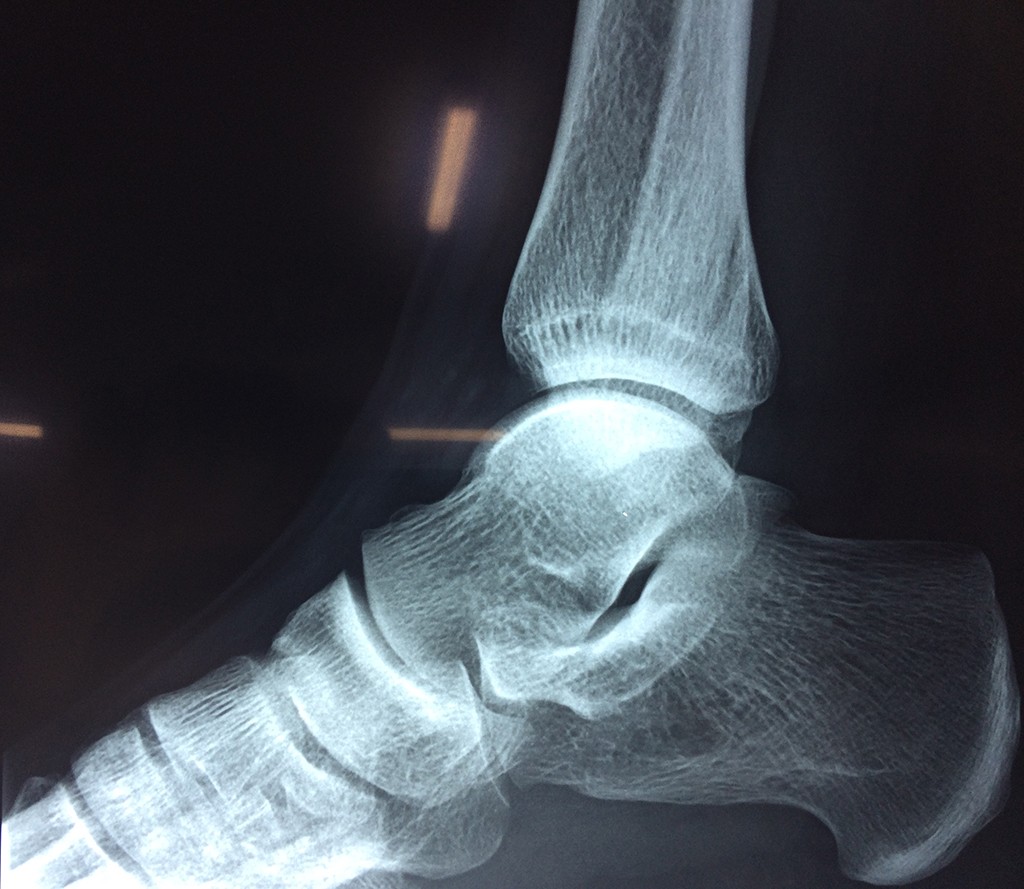

Una fractura de tobillo es la rotura de uno o más de los huesos del tobillo. Estas fracturas pueden ser:

- Parciales (el hueso está sólo parcialmente fisurado, no del todo).

- Completas (el hueso está perforado y está en 2 partes).

- Los extremos de los huesos están desalineados entre sí (desplazados).

- La fractura se extiende hasta la articulación del tobillo (fractura intra-articular).